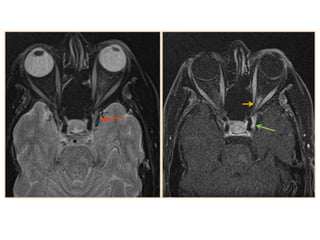

• #20 Carotid-cavernous fistula: axial T2-wi (a) of a carotid-cavernous fistula appearing as a heterogeneous signal with flow voids of the right cavernous sinus (black arrows). Note the dilatation of the superior ophthalmic vein (dotted arrow) and the carotid-cavernous fistula (white arrow) on an arterial TOF of another patient with a carotid-cavernous fistula (b)